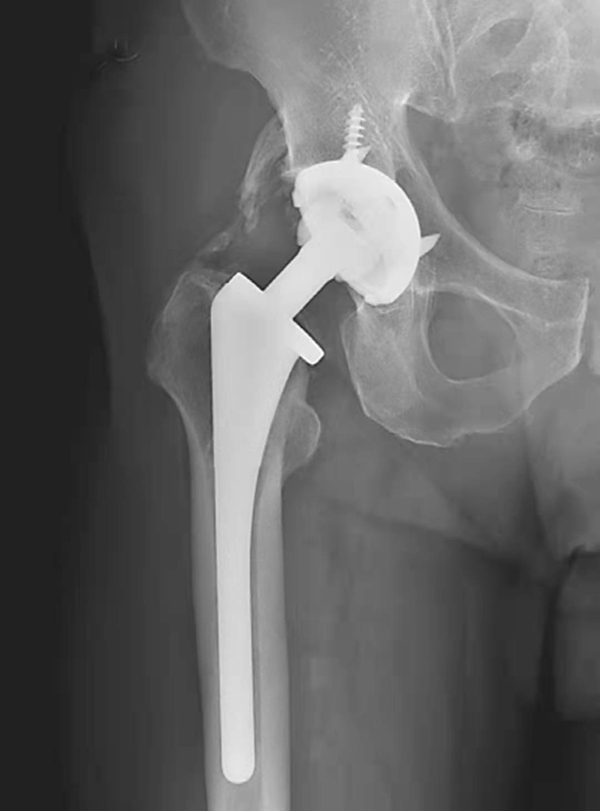

图2 无菌性松动

平片,示右侧股骨上段骨质疏松,人工股骨柄周围明显骨质吸收,透亮带明显增宽,髋臼杯位置未见改变